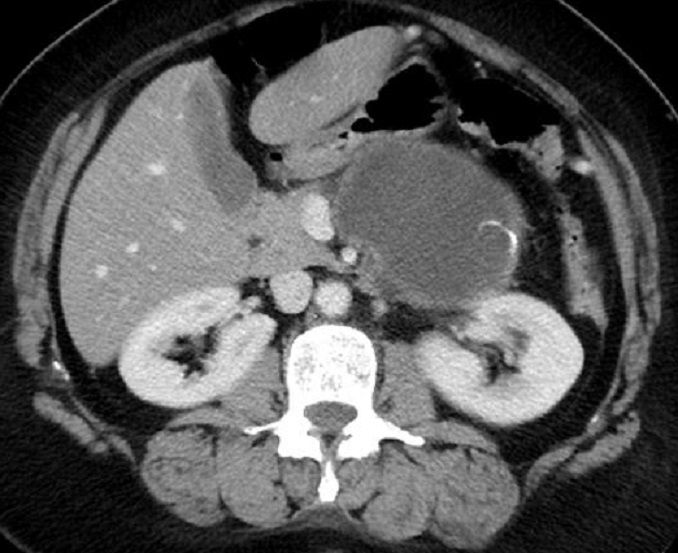

Aspect radiologique du cystadenome

sereux multikystique de la tete du pancreas . La

tumeur est comporte par des kyste a moindre 2cm a

hypodense , de contour et cloison septal interne

sont nette , Image radiologique TDM non contrast

intraveineuese , coupe axiale . |